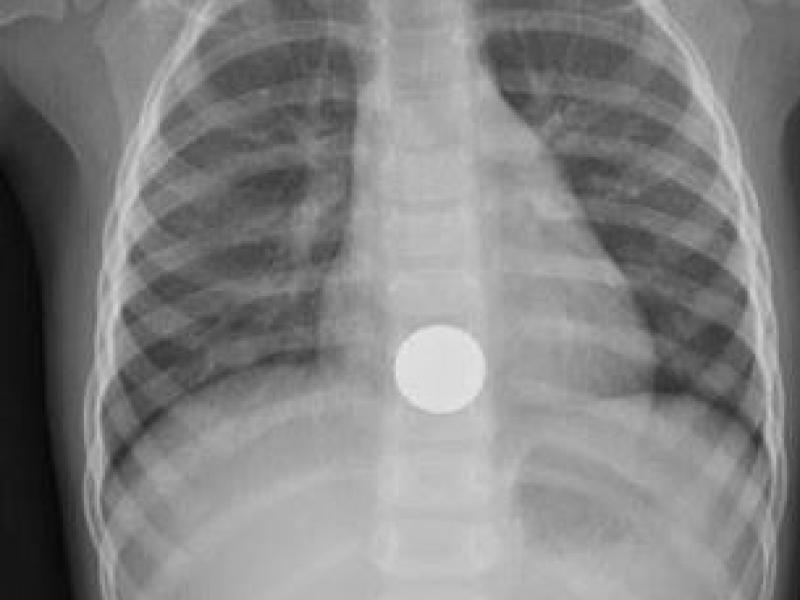

What's the Diagnosis? By Dr. Lynn Manganiello

A 2 year old F presents to the ED with her parents with